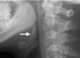

Tonsillar cancer

Oropharyngeal cancer (OPC), also known as oropharyngeal squamous cell carcinoma (OPSCC) and tonsil cancer, is a disease in which abnormal cells with the potential to both grow locally and spread to other parts of the body are found in the oral cavity, in the tissue of the part of the throat (oropharynx) that includes the base of the tongue, the tonsils, the soft palate, and the walls of the pharynx.The two types of oropharyngeal cancers are HPV-positive oropharyngeal cancer, which is caused by an oral human papillomavirus infection; and HPV-negative oropharyngeal cancer, which is linked to use of alcohol, tobacco, or both.Oropharyngeal cancer is diagnosed by biopsy of observed abnormal tissue in the throat. OPC is staged according to the appearance of the abnormal cells on the biopsy coupled with the dimensions and the extent of the abnormal cells found. [Source: Wikipedia ]